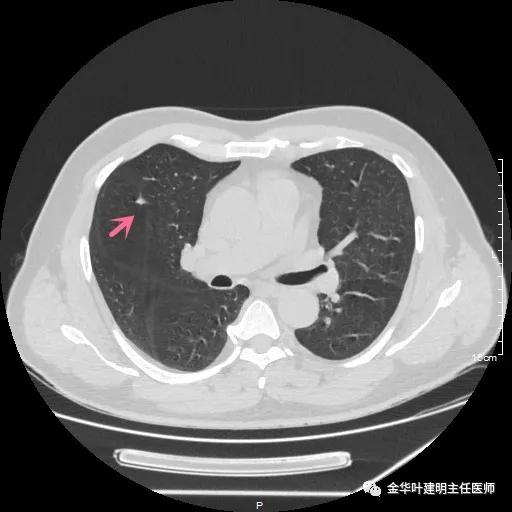

患者年纪虽然不大,但合并存在肾病综合征、高血压、高血压性心脏病、高脂血症、动脉硬化伴斑块、甲状腺结节、前列腺增生及脂肪肝、糖耐量异常等一系列问题。关键是后续需要大剂量激素治疗。下面是其2019年9月份的平扫CT图像,层厚1.2毫米:

可见是右肺中叶的微小实性结节,不规则形,密度甚高,无明显磨玻璃成份,也非圆形或类圆形,明显是一纤维增生性质的结节,肯定是可以随访观察的。当然去年也没报需警惕,或叫我们胸外科会诊。但再来看今年的图像,也是薄层扫描,层厚同样是1.2毫米: